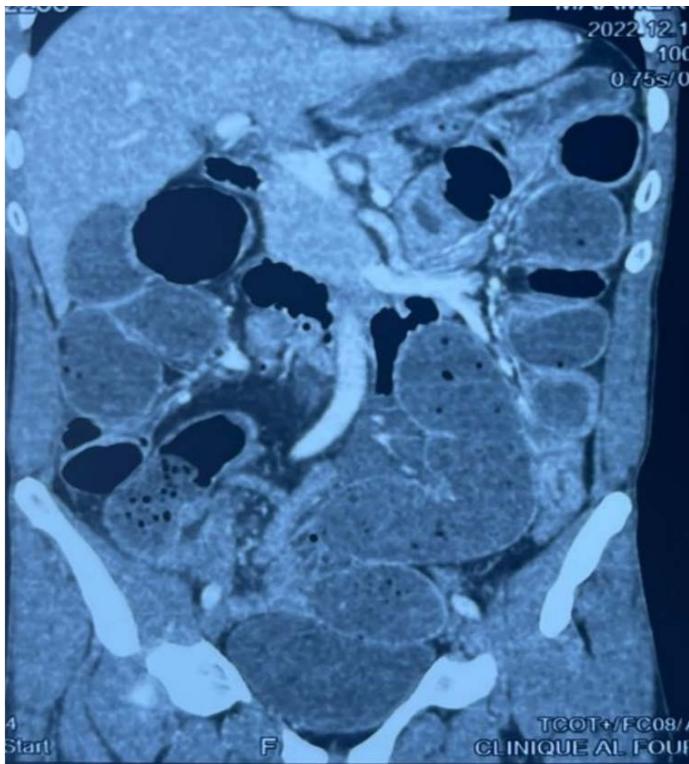

Abdominal CT scan showed small and large bowel distention with a caliber disparity in the right iliac fossa and air-fluid levels.

Figure 1: Caliber disparity in the right iliac fossa